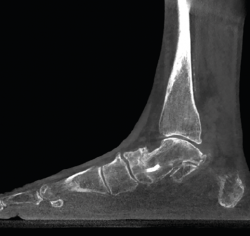

mact.1301.fs2105003-figura2.png

Figura 2. Severo pie plano valgo bilateral con pinzamiento fibular.

• Pie plano valgo del adulto. Permite la valoración de la articulación subtalar, el valgo del retropié y la inestabilidad de la columna medial (Figuras 2 y 3).